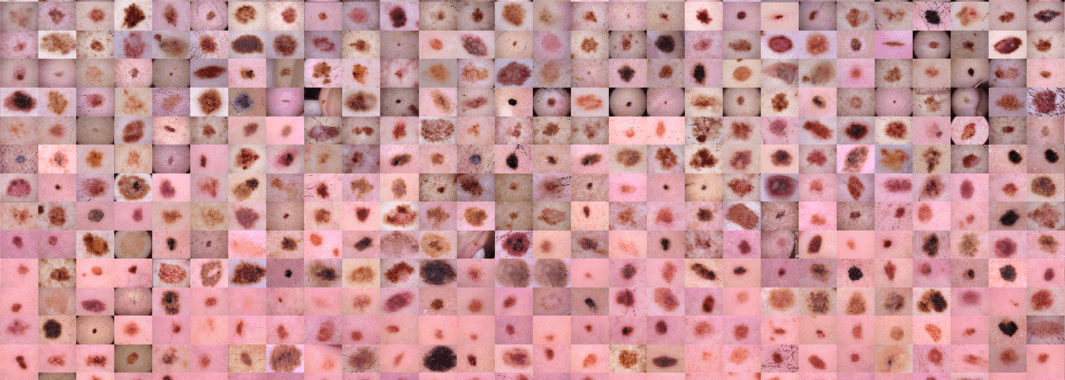

AI วินิจฉัยโรคมะเร็งผิวหนัง 7 ชนิด ความแม่นยำ 94% Melanoma Skin Cancer HAM10000 Dermatoscopic Pigmented Lesions – Image Classification ep.8

โรคมะเร็งผิวหนัง นับเป็นปัญหาใหญ่ในทางสาธารณสุข ทุก ๆ ปี ในประเทศสหรัฐอเมริกา เราจะพบผู้ป่วยใหม่ มากกว่า 5 ล้านราย มะเร็งผิวหนัง Melanoma เป็นมะเร็งผิวหนังชนิดที่ร้ายแรงที่สุด เป็นมะเร็งผิวหนังชนิดที่คร่าชีวิตคนมากที่สุด ในปี 2015 ทั่วโลก มีการตรวจพบ Melanoma มากกว่า 350,000 เคส โดยมีผู้ป่วยเสียชีวิต 60,000 คน ถึงแม้อัตราการเสียชีวิตจะสูง แต่ถ้ามีการวินิจฉัยโรคมะเร็งผิวหนังที่ง่ายขึ้น ตรวจพบตั้งแต่ระยะเริ่มต้น และรักษาได้อย่างทันท่วงที เราจะสามารถเพิ่มอัตราการรอดชีวิต ได้มากกว่า 95% ใน ep นี้ เราจะมาสร้าง AI โมเดล Deep Learning ที่จะวินัจฉัยโรคมะเร็งผิวหนัง ด้วยการจำแนกรูปถ่ายผิวพรรณ ที่มีความผิดปกติของเม็ดสี ว่าเป็นโรคอะไรใน 7 โรคที่กำหนด ด้วยความแม่นยำ 94%